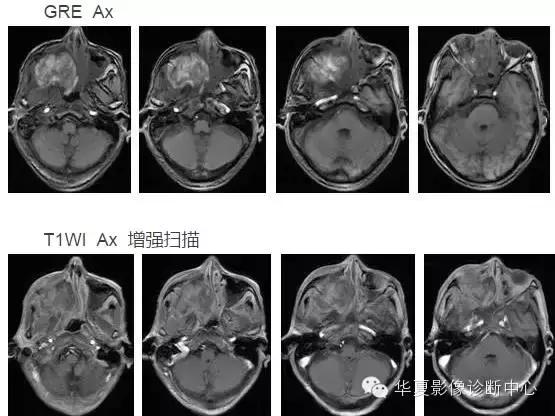

颅内黑色素瘤

中枢神经系统内原发性黑色素瘤少见, 因脑和脊髓的软脑( 脊) 膜及蛛网膜上含有黑色素细胞, 黑色素可发生于软脑( 脊) 膜的任何部位,故其发生部位常位于脑( 脊髓) 表面, 沿软脑膜生长; 而继发性黑色素瘤同一般转移性肿瘤, 常位于灰白质交界区。

影像表现:常表现为短 T1 高信号, 短T2WI 低信号,又因为黑色素瘤是富血管性肿瘤, 增强扫描常表现为明显强化。

★但少数肿瘤也不具备上述典型信号特征,主要原因是肿瘤内黑色素量多少影响。只有当黑色素瘤中黑色素细胞超过一定含量( ﹥ 10% ) 时, 才会出现黑色素瘤的典型MRI表现; 不典型的黑色素瘤因其黑色素含量较少,不足以缩短T1、T2弛豫时间,而表现为长T1低信号、长T2高信号。

依据黑色素瘤的不同 MRI 影像表现将其分为 4 种类型: ( 1) 黑色素型。该黑色素瘤因含有丰富的黑色素颗粒, MRI表现较典型,即短 T1 高信号,短 T2 低信号。( 2) 无黑色素型。因该类黑色素瘤不含黑色素颗粒或含量较低,MRI 表现为长 T1 低信号,长 T2 高信号; ( 3) 混合型。黑色素型和非黑色素型两者的混合; ( 4) 出血型。表现为血肿不同时期的信号特征, 该黑色素瘤 MRI增强扫描表现为不均匀环状或弥漫性强化